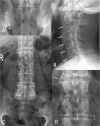

Imaging is an integral part of the management of patients with ankylosing spondylitis and axial spondyloarthritis. Characteristic radiographic and/or magnetic resonance imaging (MRI) findings are key in the diagnosis. Radiography and MRI are also useful in monitoring the disease. Radiography is the conventional, albeit quite insensitive, gold standard method for assessment of structural damage in spine and sacroiliac joints, whereas MRI has gained a decisive role in monitoring disease activity in clinical trials and practice. MRI may also, if ongoing research demonstrates a sufficient reliability and sensitivity to change, become a new standard method for assessment of structural damage. Ultrasonography allows visualization of peripheral arthritis and enthesitis, but has no role in the assessment of axial manifestations. Computed tomography is a sensitive method for assessment of structural changes in the spine and sacroiliac joints, but its clinical utility is limited due to its use of ionizing radiation and lack of ability to assess the soft tissues. It is exciting that with continued dedicated research and the rapid technical development it is likely that even larger improvements in the use of imaging may occur in the decade to come, for the benefit of our patients.